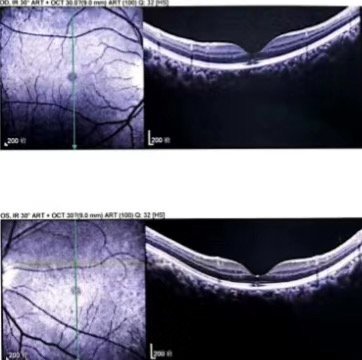

入院后,赵铁英院长给予小秀改善微循环、营养支持治疗用药。“她的视力出现下降,当时矫正视力下降到0.8,经过十多天的治疗,她的暗区变淡了,不特别注意的情况下几乎消失了。通过这段时间她的症状描述,以及我们看到的视网膜各层细胞结构的修复情况,很有信心应该能修复到正常的状态。”赵铁英院长告诉记者。

出院当天,小秀也开心地告诉记者“我现在眼前盘状“暗区”明显缩小了,今天做检查视力也由0.8提升至1.0,赵院长说我可以出院回家了。这和我来之前相比,真的是好太多了,我为赵院长点一个大大的赞。”

(小秀双眼治疗前后视网膜断层扫描图像)